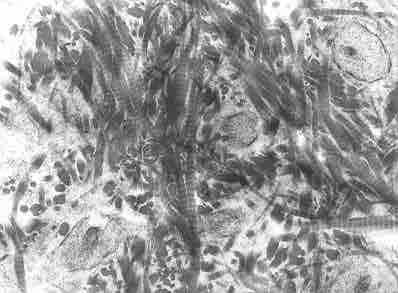

Woven bone is characterized by the irregular organization of collagen fibers and is mechanically weak.

This is a photo of woven bone seen through a microscope. Woven bone is characterized by the irregular organization of collagen fibers seen in this picture, and it is mechanically weak.